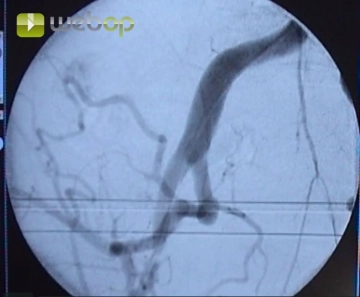

Punktion der Arteria femoralis communis in Richtung Arteria iliaca externa. Einführen einer 6F-Schleuse nach Seldinger. Hochführen des Führungsdrahtes unter Durchleuchtungskontrolle.